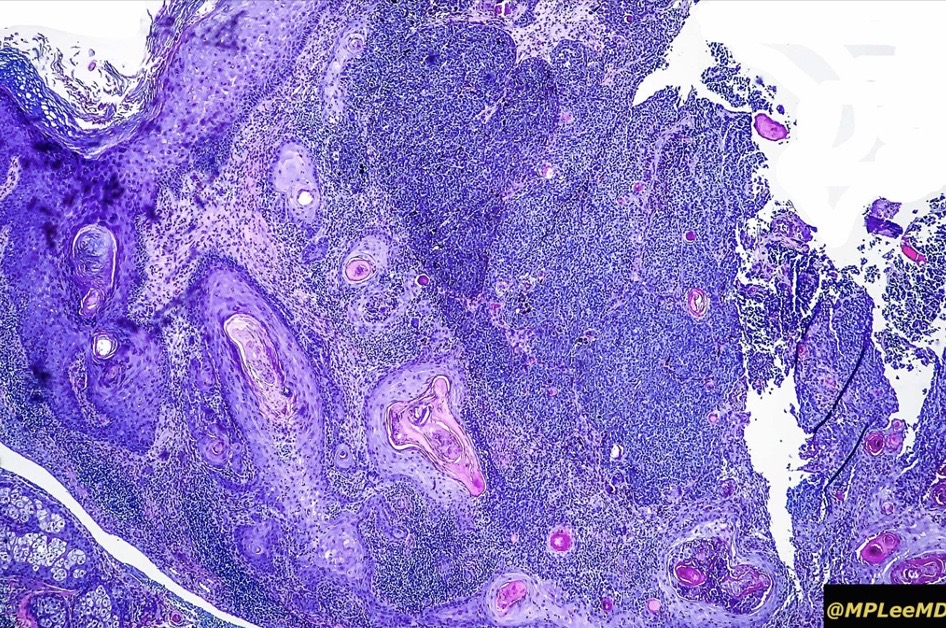

An exceedingly rare collision tumor composed of an admixture of squamous cell carcinoma/basal cell carcinoma/trichoblastoma respectively and melanoma. Although most appear to have behaved in a benign fashion, a malignant basomelanocytic tumor is illustrated below. More cases will be need to be stidies/published before the true biological behavior of this group of tumors can be satisfactorily elucidated. I think that complete excision should be the rule and a careful follow-up recomended.

•Sun-damaged skin of head & neck presenting as a keratotic papule or nodule

•Most cases appear to be indolent but a rare malignant basomelanocytic tumor example has been documented

Basomelanocytic tumor

Squamomelanocytic tumor